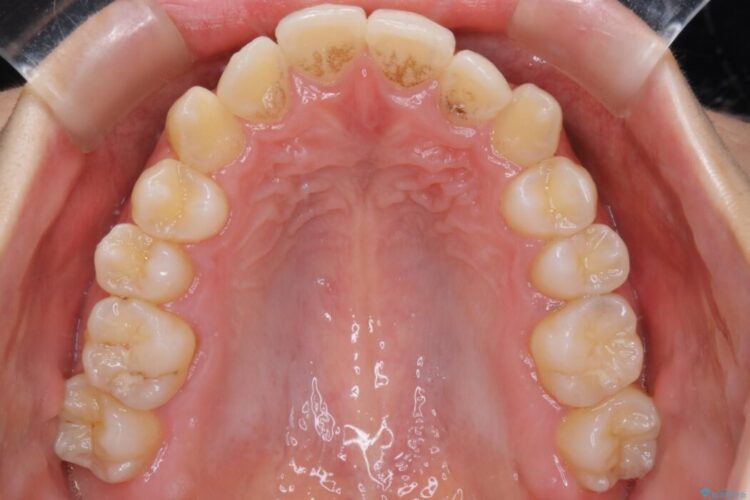

検査したところ叢生度合いから抜歯をせずとも治療が可能と判断しましたので、インビザラインでの非抜歯矯正を行う方針としました。

治療後写真を見ても歪みが解消され、歯列弓がきれいに整ったのが分かると思います。インビザラインをしっかりと装着されていたこともあり、矯正としては短期間の治療となりました。